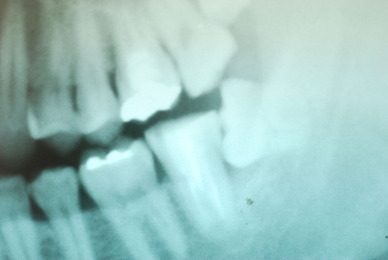

お口の中から差し歯、入れ歯、詰め物を追放しましょう!

口の中の病気を治し、病気を興さない医療を目指します。

「川崎市の入れ歯なら新丸子西口歯科医院へ」

「顎関節症は新丸子西口歯科医院へ」